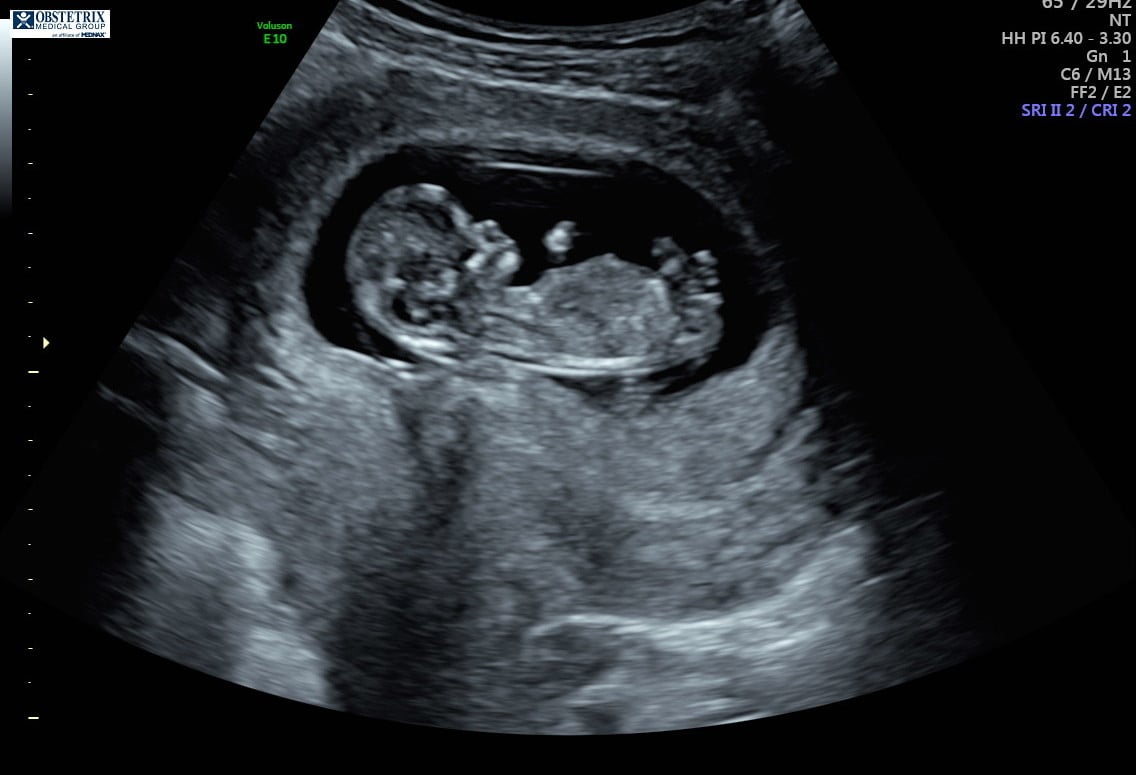

Hello! The photo is from my 12 week ultrasound. I’ve been reading up on the nub theory because I’m dying to know the sex, but I can’t decide if it looks more girly or boyish. Any thoughts are appreciated!!!!

“Experts” on the nub theory my friend. Yes, I have talk to doctors about it. Yes, some do believe in the nub theory while others are afraid to guess because they are afraid to guess wrong and upset anyone which makes sense. No, it is not always accurate and if you try the nub theory generally you know not to take to it too seriously until the anatomy scan. Also this theory will not hurt the baby so no harm done. But if you can’t handle the possibilty of a wrong guess then don’t even try asking for a guess. It’s for fun. Have you read up on it even? The nub sits flat with the back if it’s a girl and it’s angled up from the back if it’s a boy. I have 2 girls and 1 boy so I am pretty sure it’s not “luck” just really good scans! The “experts” on the nub theory have guessed correctly with my ultrasound pictures. I have also done the NT scans which is around the right time to make a guess with the nub about 11-13 weeks I believe. The doctor agreed that it can be accurate if done properly. You must have a perfect nub picture ( a full body side view of fetus without their back curled during 11-13 weeks) to get a pretty accurate guess. Notice my use of guess? Yes, still 50/50 and yes, doctors still get the anatomy scan wrong too so you can’t be 100% sure until birth if you are want total accUracy. Do some reading up. I found it very interesting when I had my first child. But it is called a theory for reason.

“Experts” on the nub theory my friend. Yes, I have talk to doctors about it. Yes, some do believe in the nub theory while others are afraid to guess because they are afraid to guess wrong and upset anyone which makes sense. No, it is not always accurate and if you try the nub theory generally you know not to take to it too seriously until the anatomy scan. Also this theory will not hurt the baby so no harm done. But if you can’t handle the possibilty of a wrong guess then don’t even try asking for a guess. It’s for fun. Have you read up on it even? The nub sits flat with the back if it’s a girl and it’s angled up from the back if it’s a boy. I have 2 girls and 1 boy so I am pretty sure it’s not “luck” just really good scans! The “experts” on the nub theory have guessed correctly with my ultrasound pictures. I have also done the NT scans which is around the right time to make a guess with the nub about 11-13 weeks I believe. The doctor agreed that it can be accurate if done properly. You must have a perfect nub picture

( a full body side view of fetus without their back curled during 11-13 weeks) to get a pretty accurate guess. Notice my use of guess? Yes, still 50/50 and yes, doctors still get the anatomy scan wrong too so you can’t be 100% sure until birth if you are want total accUracy. Do some reading up. I found it very interesting when I had my first child. But it is called a theory for reason.